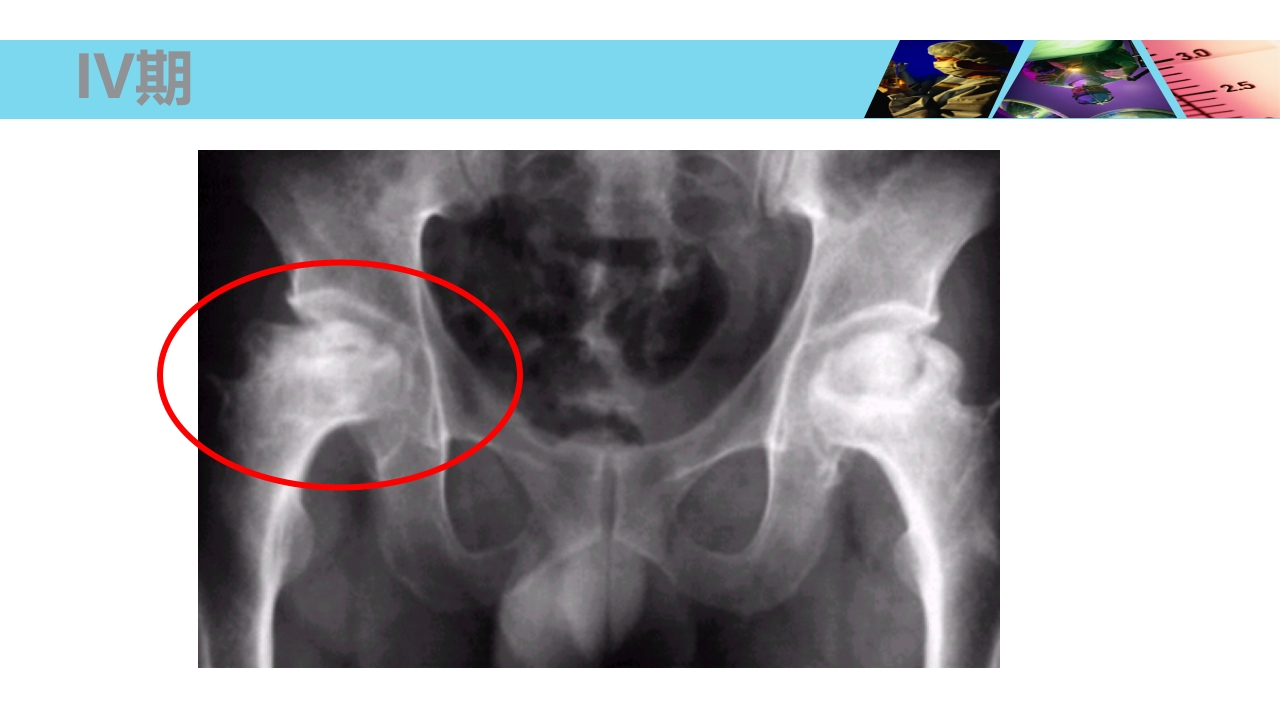

股骨头无菌性坏死 Necrosis of Femoral Head xxxx医院 骨科 WHO/WHAT/WHY/HOW? OUTLINE 1 2 3 4 5 概念及流行病学 病因 发病机制及病理 临床表现及诊断 治疗 概 念 Concept 股骨头坏死、股骨头缺血性坏死、股骨头无菌性坏 死等(Necrosis of Femoral Head) 不同病因破坏了股骨头血供所造成的最终结果。 损伤-修复(Damage-Repair) 4 股骨头血供 由旋股内、外侧动脉所发出的支持带动脉,占股骨头血供的70%。 股深动脉所发出的股骨滋养动脉,占股骨头血供的25%。 闭孔动脉或旋股内侧动脉所发出的股骨头韧带动脉,占股骨头血供的5%。 股骨头血供 一、流行病学 Epidemiology 世界骨科三大难题之一 在美国,年人均发生率在 2 万 -3 万之间,约有 5%-12% 的髋关 节置换...